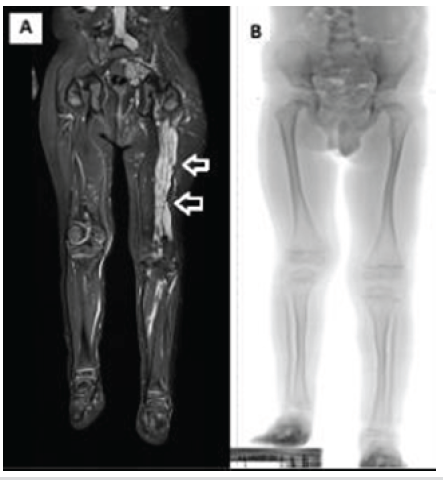

A 5-year-old boy with genetically confirmed NF1 has been under regular follow-up in the pediatric orthopedic department. The patient was diagnosed with NF1 at 1.5 years of age after a positive family history (father NF1 diagnosis). Considering clinical examination, the patient had a small café au lait spot (<5 mm) on the back, no scoliosis, or congenital pseudarthrosis of the tibia. However, a PN involving the left lower limb (Fig. 1a) had led to increased local vascularity, resulting in soft tissue and osseous overgrowth of the affected limb. This progressive overgrowth had caused a limb length discrepancy (LLD) of approximately 4.5 cm, with the left leg being longer (Fig. 1b). The patient had been treated with selumetinib (20 mg twice daily) as part of ongoing treatment to inhibit growth of PN since the age of 3.5 years old, but without a significant reduction of the neurofibromas volume.

Figure 1: (a) Magnetic resonance imaging of both lower limbs showing extensive plexiform neurofibroma infiltration in the soft tissues of the left lower limb compared to the unaffected right side. (b) Standing radiograph, demonstrating limb length discrepancy, with the right lower limb being shorter by 4.5 cm.